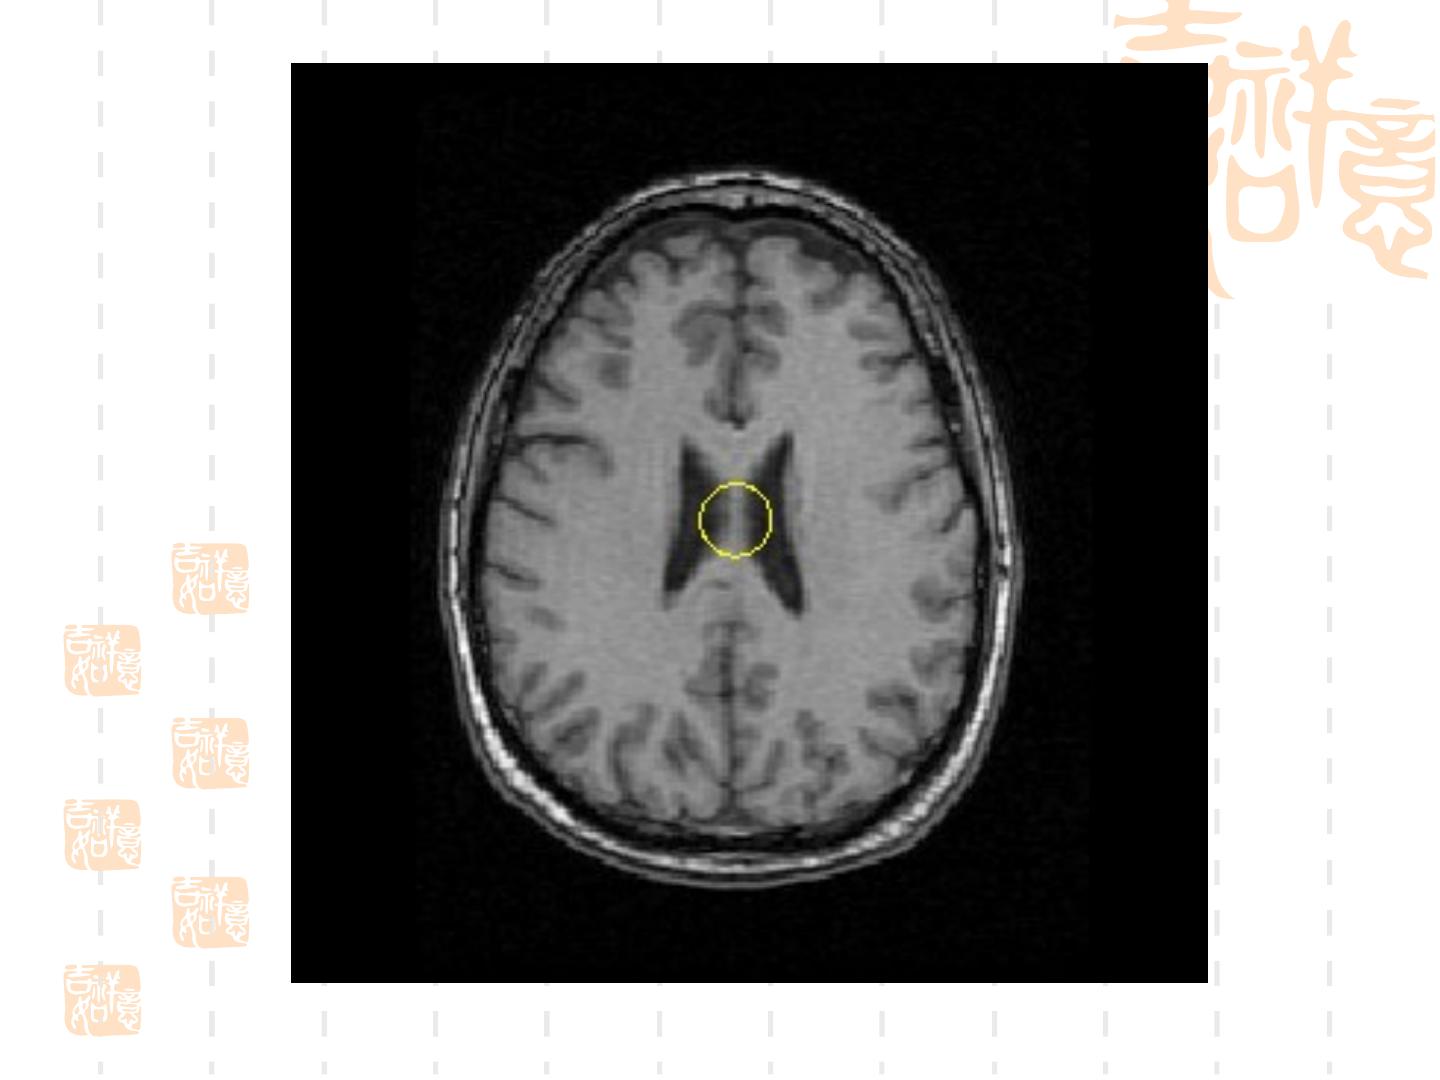

21 . 3.Snake 模型用于轮廓提取的实例